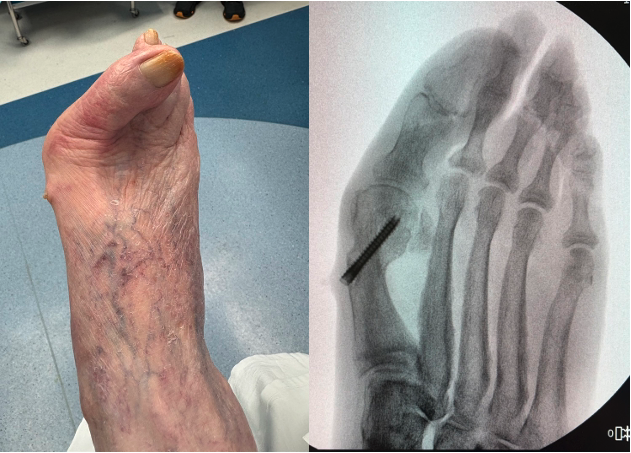

In Figures 3 A, B, C, D, the images depict the case of an elderly female who previously underwent a MIS bunion surgery. Unfortunately, she experienced a recurrent HAV and painful proximal hardware medially (Figures 3 A, B). She subsequently underwent hardware removal and revisional MIS bunion surgery (Figure 3 C, D).